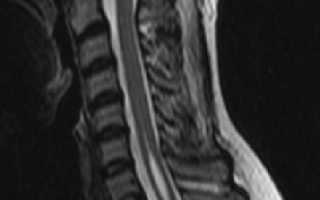

Сирингомиелия